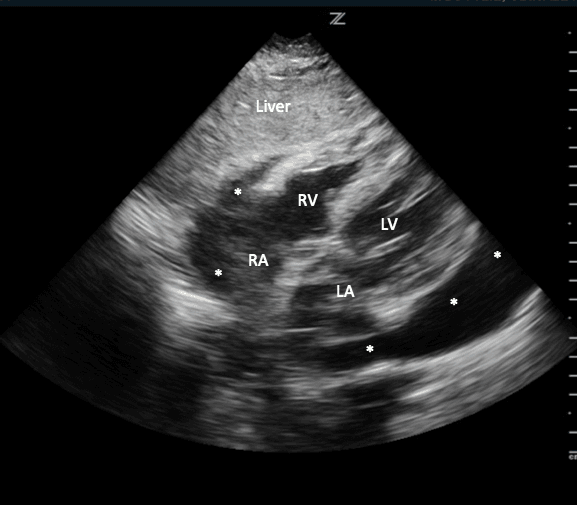

Für diese Ansicht kann entweder die Phased-Array-Sonde oder die krummlinige Sonde verwendet werden. Für das Subxiphoid in der formalen echokardiographischen Ausrichtung zeigt der Sondenindikator auf die linke Seite des Patienten. Beginnen Sie damit, den Subxiphoid-Prozess zu finden. Platzieren Sie die Porbe inferior und rechts vom Xiphoid-Prozess des Patienten. Üben Sie Druck nach unten aus, während Sie den Kopfschmerz anwinkeln und in Richtung der linken Schulter des Patienten (Bild 12).

Verwenden Sie die Leber als akustisches Fenster, um das Bild zu verbessern. Der obere Teil des Bildschirms zeigt die Leber des Patienten. Unmittelbar unterlegen zur Leber wird der rechte Ventrikel des Patienten sein und darunter kann man den linken Ventrikel identifizieren. Je nach Blickwinkel kann man in dieser Ansicht auch das rechte und linke Atrium visualisieren (Bild 13).

Subxiphoid markierte Strukturen

Das Abrufen der subxiphoiden Ansicht kann aus zahlreichen Gründen schwierig sein. Dazu gehören der Körperhabitus des Patienten, Darmgas, freie Luft im Thorakoabdominalbereich oder die Unfähigkeit des Patienten, die Untersuchung infolge von Schmerzen zu tolerieren.

Die subxiphoide Ansicht ist die beste Ansicht, um das Vorhandensein oder Fehlen eines Perikardergusses zu beurteilen. 2,17,18 Flüssigkeit aus einem Perikarderguss sammelt sich zunächst in den abhängigsten Teilen des Perikards, nämlich den unteren und hinteren Aspekten, normalerweise um den rechten Vorhof. 19,20 Volumina von nur 15-35cc Flüssigkeit im Perikard können mit Herzultraschall am Krankenbett detektiert werden. 21 Wenn ein Perikarderguss vorhanden ist, sehen Sie auf einer subxiphoiden Ansicht Flüssigkeit zwischen dem Leberlappen und dem rechten Ventrikel am oberen Bildschirmrand (Bild 14).